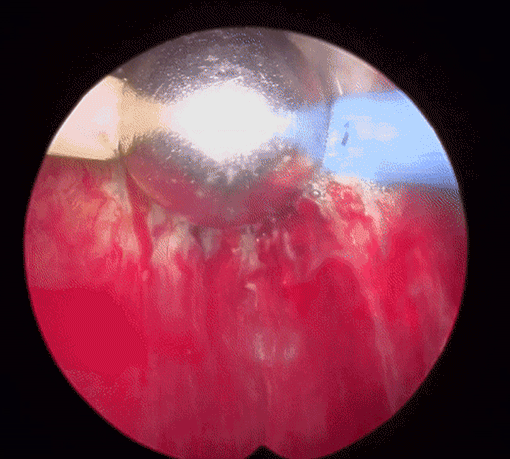

플라즈마 기화술(TURis Plasma Vaporization)은 70°C 이하의 낮은 온도에서 플라즈마를 발생시켜 비대해진 전립선 조직을 기화시키는 매우 안전하면서도 확실한 치료효과를 기대할 수 있는 혁신적인 시술 기법입니다.

70°C 이하의 낮은 온도로 조직이 기화되기 때문에 기존의 레이저 수술과 달리 고열로 인한 주변 조직 손상이 없습니다. 직접 접촉 없이 비대된 전립선 조직을 정확하고 신속하게 제거할 수 있으며 시술시간과 회복기간도 짧고 통증이 적다는 장점이 있습니다. 또한 출혈이 거의 없고, 조직 기화에서 오는 부작용도 미미할 만큼 낮습니다.

플라즈마를 활성화 상태로 후방으로 이동하고, 비활성화 상태로 전방으로 이동하며 조직을 제거 합니다.

플라즈마 장비를 회전시키며 치료부위를 넓혀줍니다.

지혈과 치료부위를 확인하고 치료를 마무리합니다.